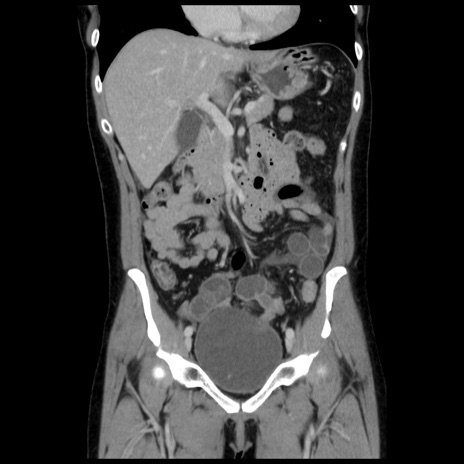

症例10(冠状断像)

【症例】 50歳代女性

【主訴】 腹痛

【現病歴】前日生レバーを食べた。今朝に排便あり。 昼前に突然発症の腹痛を生じ、当院救急外来を受診した。

【既往歴】 子宮筋腫にてで子宮全摘後

【身体所見】 意識清明、腹部:平坦、軟、下腹部やや左を中心に圧痛・反跳痛あり、筋性防御あり

【データ】WBC 7800、CRP 0.07